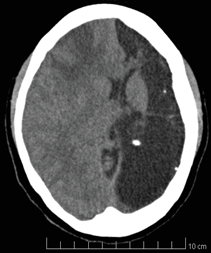

A la revisión por sistemas no se evidencian datos de interés; al examen físico paciente alerta, consciente, orientada, hidratada, sin signos de dificultad respiratoria, fuerza muscular de 3/5 en miembro superior derecho posiblemente por antecedente de polio en primer año de edad y de 5/5 en las demás extremidades, cifras tensionales de 106/63 mmHg, frecuencia cardiaca de 76 pulsaciones por minuto, frecuencia respiratoria de 18 respiraciones por minuto, ruidos cardiacos rítmicos sin soplos, ruidos respiratorios sin agregados pulmonares, abdomen blando no doloroso a la palpación, altura uterina de 31 cm, feto longitudinal cefálico derecho, con frecuencia cardiaca fetal de 155 latidos por minuto; la paciente es valorada por el servicio de ginecología quienes consideran que cursa con eclampsia pre-parto, alto riesgo obstétrico y actividad uterina pretérmino, por lo cual se continúa manejo neuroprotector con sulfato de magnesio, fenitoína y manejo antihipertensivo; además se realiza una Tomografía Axial computarizada (TC) y un electroencefalograma (EEG), este último sin alteraciones; pero de forma incidental en la tomografía axial computarizada se encuentra reemplazado casi la totalidad del hemisferio cerebral izquierdo por una gran zona de encefalomalacia quística antigua con calcificaciones puntiformes (Figura1) , asociada a desviación de las estructuras de la línea media hacia la izquierda y a importante dilatación del ventrículo ipsilateral; con preservación del tálamo y de las estructuras del tallo encefálico.

Figura 1. TC cerebral de corte sagital. Se observa una

extensa zona de hipodensidad próximo al LCR (8 UH)

que se extiende por los territorios vasculares de la arteria

cerebral anterior, media y posterior del lado izquierdo.

Que no se asocia a efecto masa. Además de la cabeza del

caudado que está delineando el contorno de asta frontal.

Fuente: Autores.